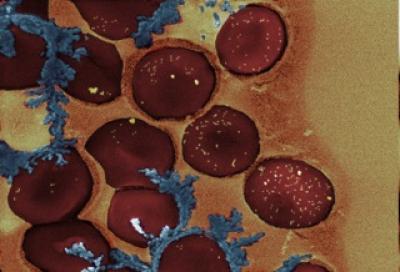

Researchers have designed tiny, light-controlled gold particles that can release DNA controls to switch blood clotting off and on. The results are reported July 24 in the open access journal PLOS ONE by Kimberly Hamad-Schifferli and colleagues from the Massachusetts Institute of Technology.

The two-way switch for blood clotting relies on the ability of two gold nanoparticles to selectively release different DNA molecules from their surface under different wavelengths of laser excitation. When stimulated by one wavelength, one nanorod releases a piece of DNA that binds the blood protein thrombin and blocks clot formation. When the complementary DNA piece is released from the other nanorod, it acts as an antidote and releases thrombin, restoring clotting activity.